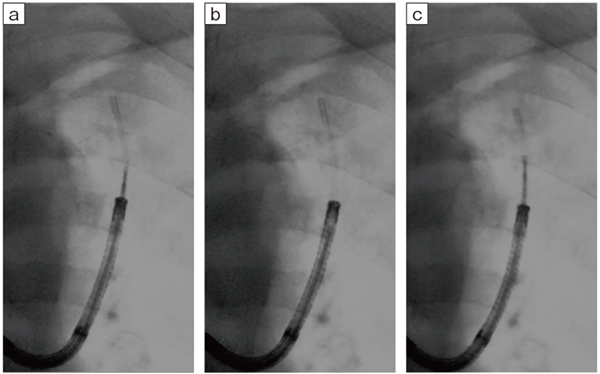

a:3.75fps b:7.5fps c:15fps

低線量の低いフレームレートでも、病変の位置確認やガイドシース先端の観察に十分な画像が得られている(Accent適用症例画像)。

(ガイドシース:GuideSheathKit2、オリンパス社製)

図10 パルス透視の各フレームレートにおける病変とデバイスの視認性